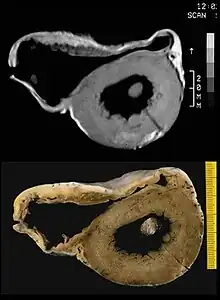

Angiography

Right ventricular angiography is considered the gold standard for the diagnosis of ACM. Findings consistent with ACM are an akinetic or dyskinetic bulging localized to the infundibular, apical, and subtricuspid regions of the RV. The specificity is 90%; however, the test is observer dependent.

Biopsy

Transvenous biopsy of the right ventricle can be highly specific for ACM, but it has low sensitivity. False positives include other conditions with fatty infiltration of the ventricle, such as long-term excessive alcohol use and Duchenne or Becker muscular dystrophy.

False negatives are common, however, because the disease progresses typically from the epicardium to the endocardium (with the biopsy sample coming from the endocardium), and the segmental nature of the disease. Also, due to the paper-thin right ventricular free wall that is common in this disease process, most biopsy samples are taken from the ventricular septum, which is commonly not involved in the disease process.

A biopsy sample that is consistent with ACM would have > 3% fat, >40% fibrous tissue, and <45% myocytes.

A post mortem histological demonstration of full thickness substitution of the RV myocardium by fatty or fibro-fatty tissue is consistent with ACM.